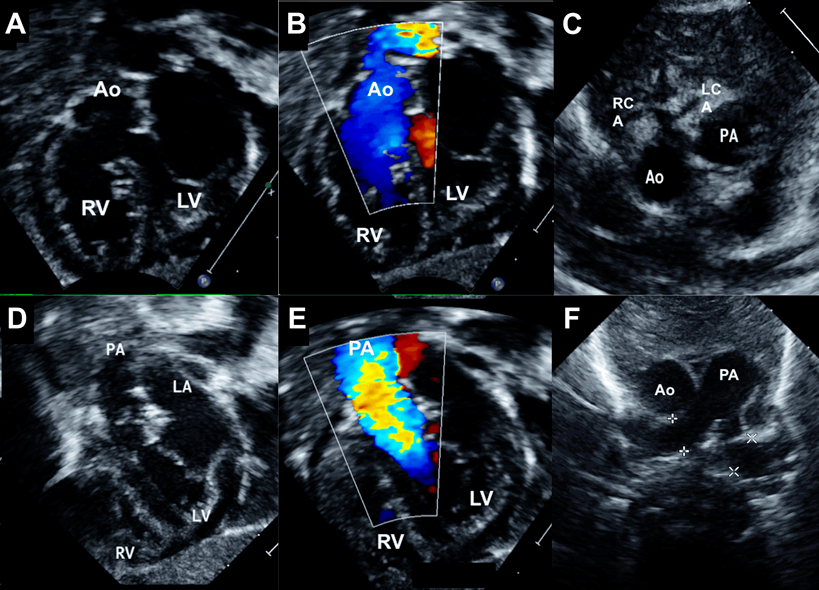

Fig. 3 Echocardiogram of second patient (Movie 3)

A leftward sweep on parasternal long axis view (A) with color flows (B) shows l-malposed aortic origin from the left ventricle and an overriding subaortic VSD. A rightward sweep (C) with color flows (D) shows a small subpulmonary conal flange below the pulmonary artery causing stenosis. Ao, aorta; LV, left ventricle; PA, pulmonary artery; RV, right ventricle.